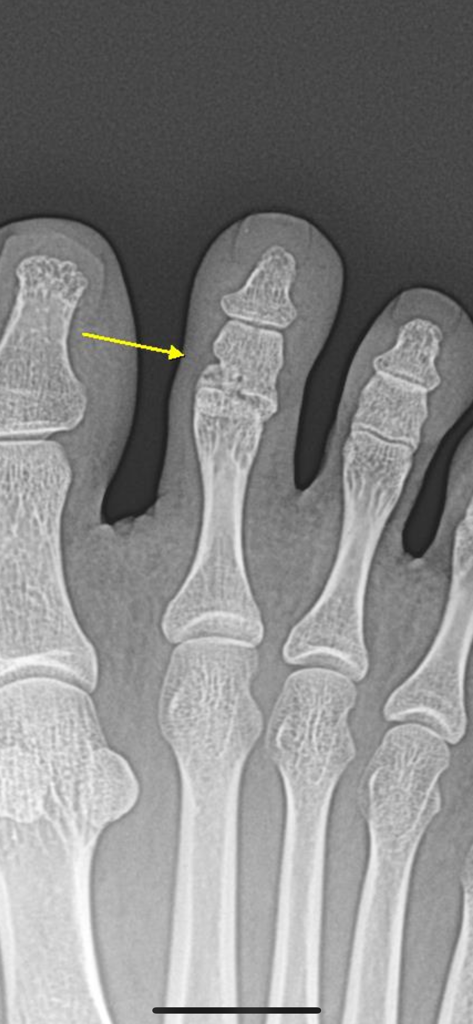

발가락 골절 이정도면 붙은 건가요?

뭘 보고 판단하는지 모르겠어서요.. 어디가 붙은건지 갈라진건지 모르겠어요 ㅜㅜ

70-80 붙었다고 하셨는데 다 붙어가고 있는건가요?

영상의 화살표가 가리키고 있는 발가락의 두번째 마디 좌측 하단부에 골절이 확인되며, 위의 사진에서는 골절부위가 유합되어가고 있는것이 관찰됩니다. 시간이 지나면 완전히 회복될 것으로 생각되니 너무 걱정하지 않으셔도 될 것 같습니다.